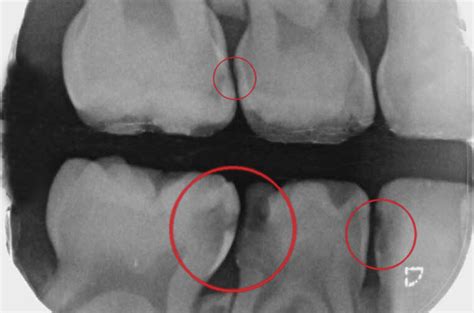

¿Cómo se ve una caries en una radiografía?

La desmineralización y destrucción de las capas del diente se observa como una imagen radiolúcida (zona negra alrededor/dentro del diente). En la imagen que señala la flecha vemos una imagen radiolúcida (oscura) que indica la falta de material dental, la presencia de una zona “hueca”. Caries.